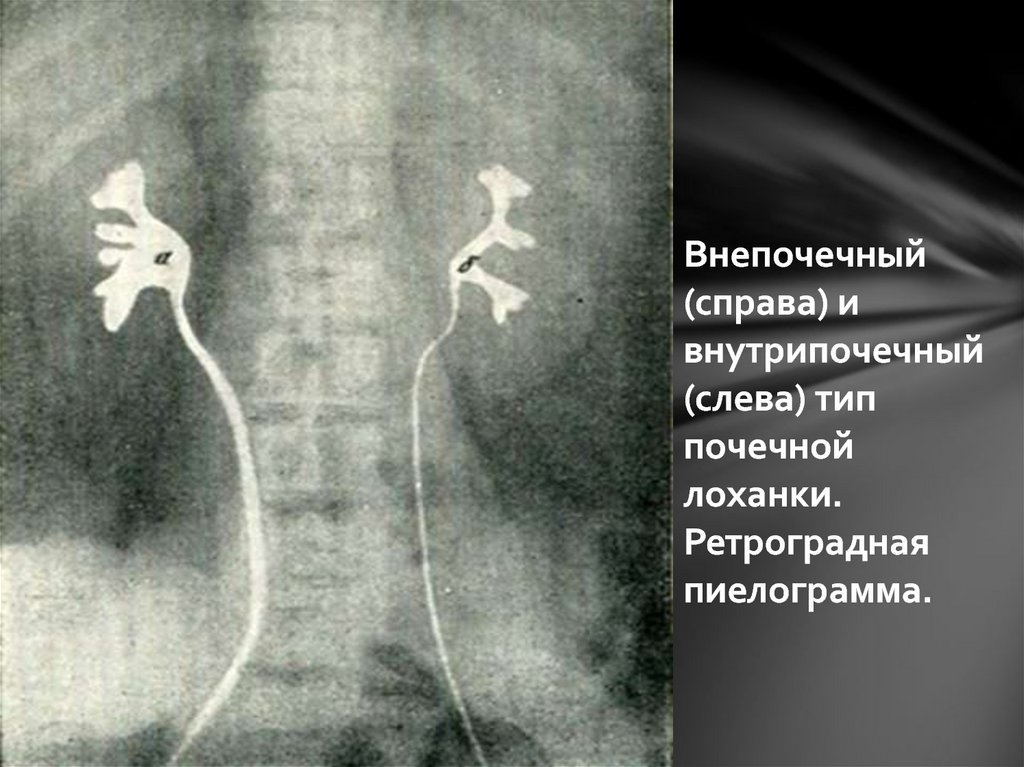

Интраренальная лоханка: рентгеновские снимки и примеры